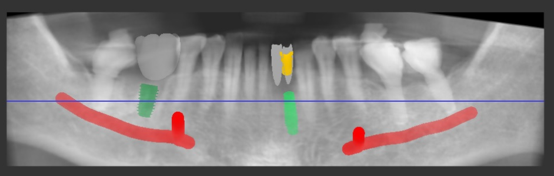

이어서 2개의 임플란트 시술 계획을

수립했고

어느 위치에 심어야 좋은 결과를

얻어낼 수 있는지

또 남아있는 인접치아들과

조화로울 수 있는지를 확인합니다.

근데.. 역시 뼈가 많이 녹아있어서

뼈 이식(GBR)은 반드시 해야 되는

상황으로 여겨졌습니다.